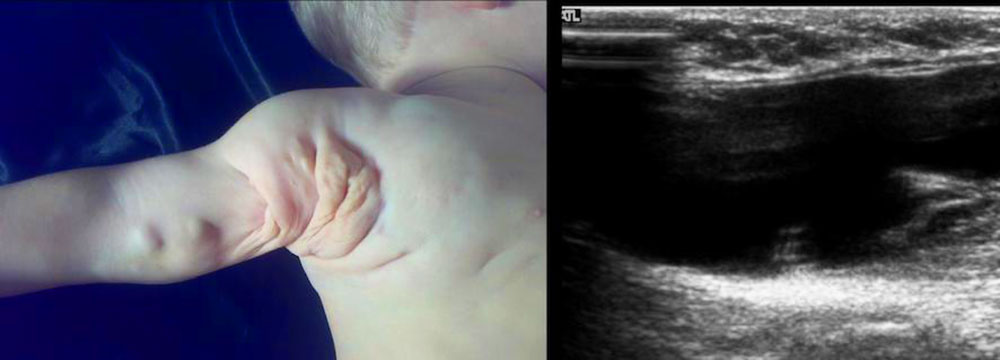

Lymphatic malformations (LM) comprise about 15% of all simple vascular malformations. They consist of more or less mature, dysplastic lymphatic vessels and can also form circumscribed, cystic masses. In infants and toddlers, they are conspicuous as circumscribed, usually skin-colored, soft swellings on various parts of the body. They feel soft to the touch since they consist of lymph-filled cystic cavities of varying size.

They manifest themselves as microcystic, macrocystic or combined micro- and macrocystic vascular anomalies. Predilection sites for lymphatic malformations are the head and neck region in 67%, followed by the trunk, chest wall, axilla and extremities in 30%. They rarely manifest themselves in deep tissues or the parenchymatous organs, where they can occur in up to 3%. A special form of lymphatic malformation is the very rare Gorham-Stout syndrome, also known as “vanishing bone disease”, in which lymphatic tissue replaces or destroys bone tissue and can lead to progressive osteolysis. In generalized lymphatic anomaly (GLA), the bones are also affected, but not in such an expansive or aggressive form as in Gorham-Stout syndrome. Internal organs may also be affected in GLA. In central conducting lymphatic anomaly (CCLA), a malformation (hypoplasia, aplasia) of central lymphatic conductors in the abdomen and/or chest causes lymphatic congestion proximal to the stenosis/occlusion. This leads to leg edema, exudative enteropathy, cutaneous lymph vesicles and/or recurrent lymphatic ascites or pleural effusion.